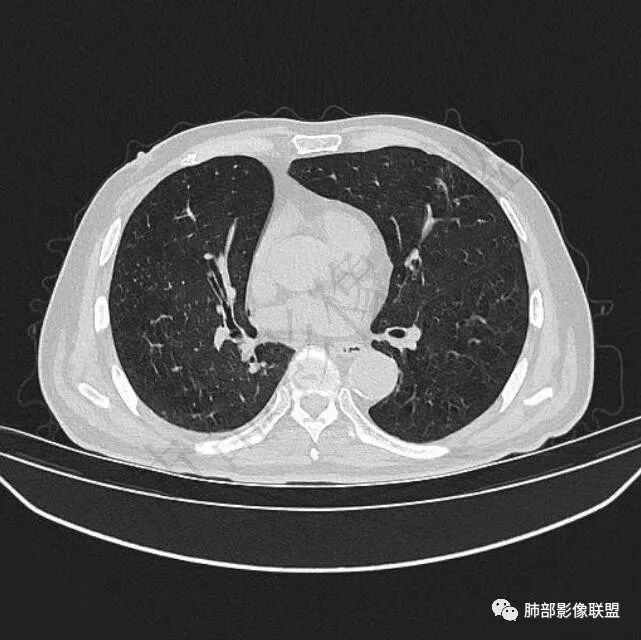

二..发现左肺上叶舌段实性密度小结节影,不规则略呈半环形,边界清楚,未见分叶、毛刺及磨玻璃晕。未见卫星病灶。